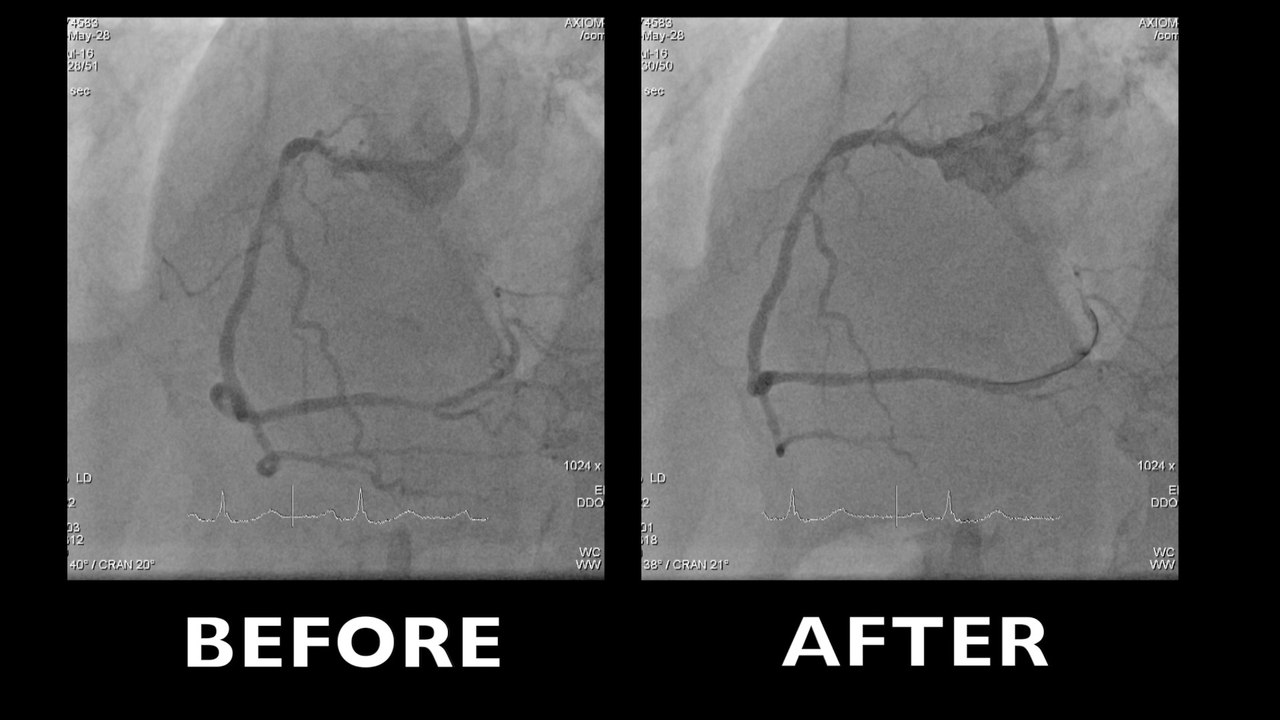

•PCI OM1  + failed attempt revascularisation CTO RAC (06/2016)

•Today 2nd attempt at CTO RAC

–J-CTO score > 3